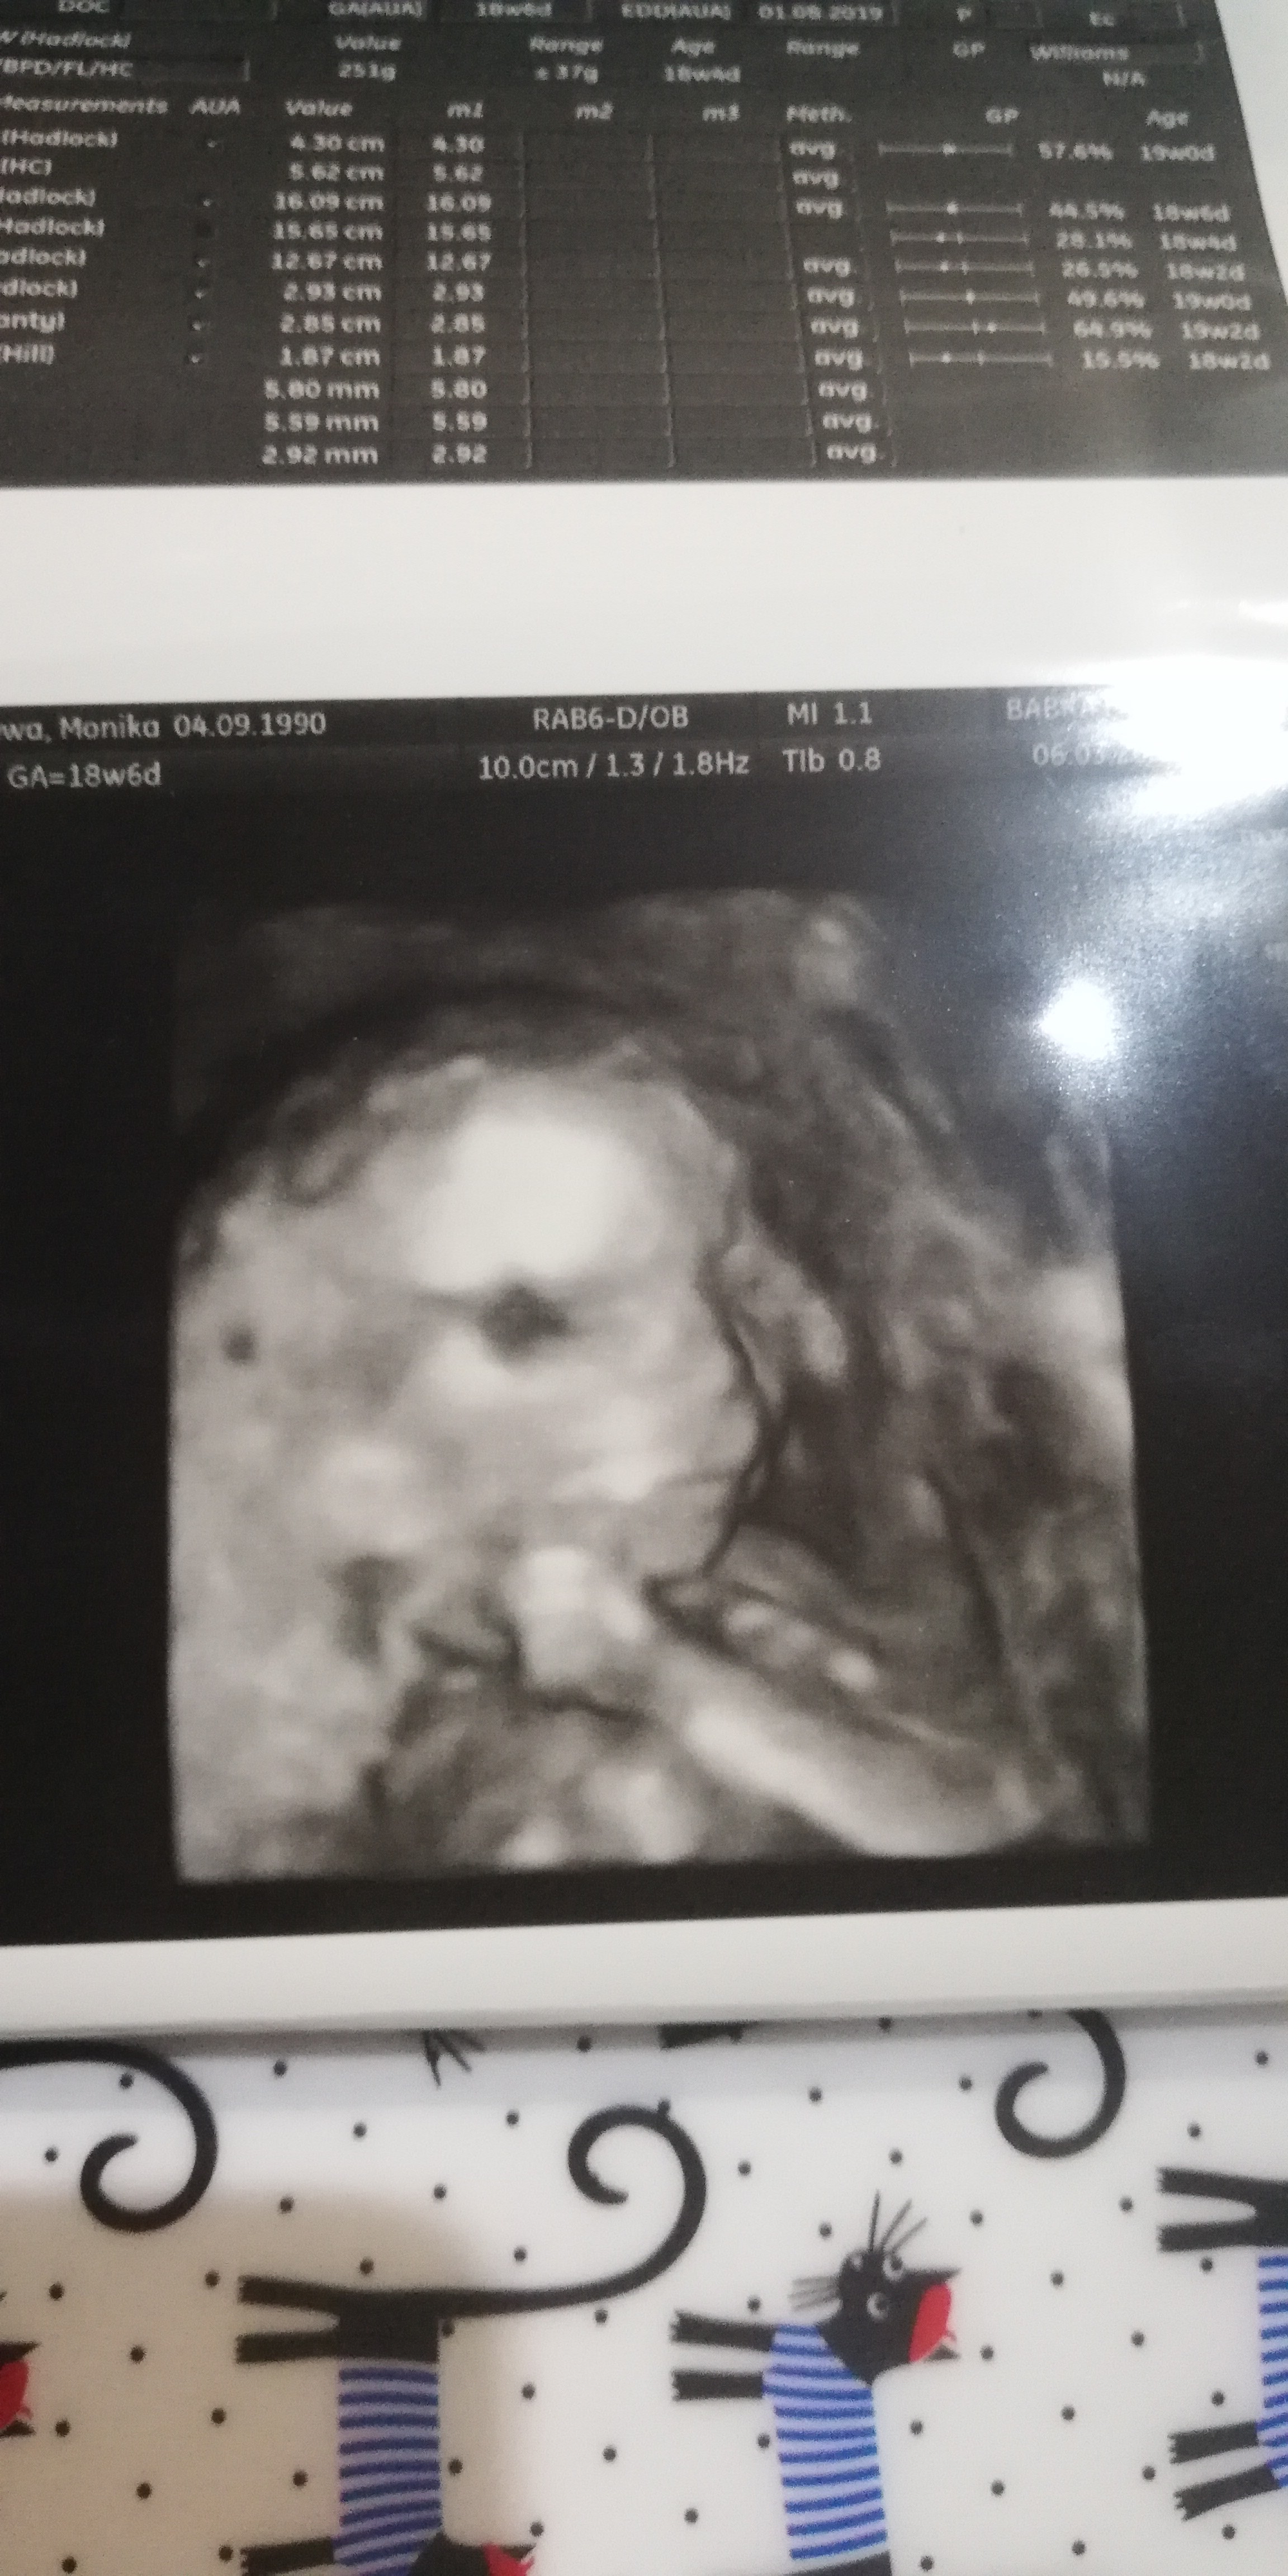

Gratulacje!Ja mieszkam na wsi pod Warszawąbyłam dziś na usg, tak sobie poszłam bo już nie mogłam wytrzymać

Dzidzia ma się wspaniale... Wygląda na zupełnie zdrową i... "uwidoczniono żeńskie narządy płciowe"! Ryczę jak bóbr. Wymarzyłam córcię i jest!

Nooo, są trochę creepyCzy tylko mnie przerażają te zdjęcia 3D?